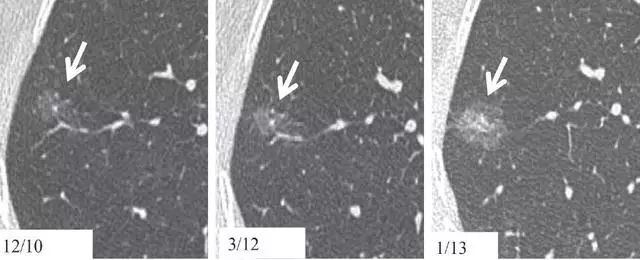

10、相隔10~15个月结节渐进表现

图 10(a)右肺中部层厚 1 mm 的 CT 横断面图像,显示一个 10 mm 大小的纯磨玻璃样结节(箭头)。(b)同一位置 15 个月后的 CT 随访图像,显示病变的不透明度只有很小增加。(c)取得 b 图 10 个月后,同一位置的 CT 图像,显示结节已发展成较大的实性结节。手术切除证实为 1A 期浸润性鳞屑样为主的腺癌(invasive lepidic predominant adenocarcinoma)。